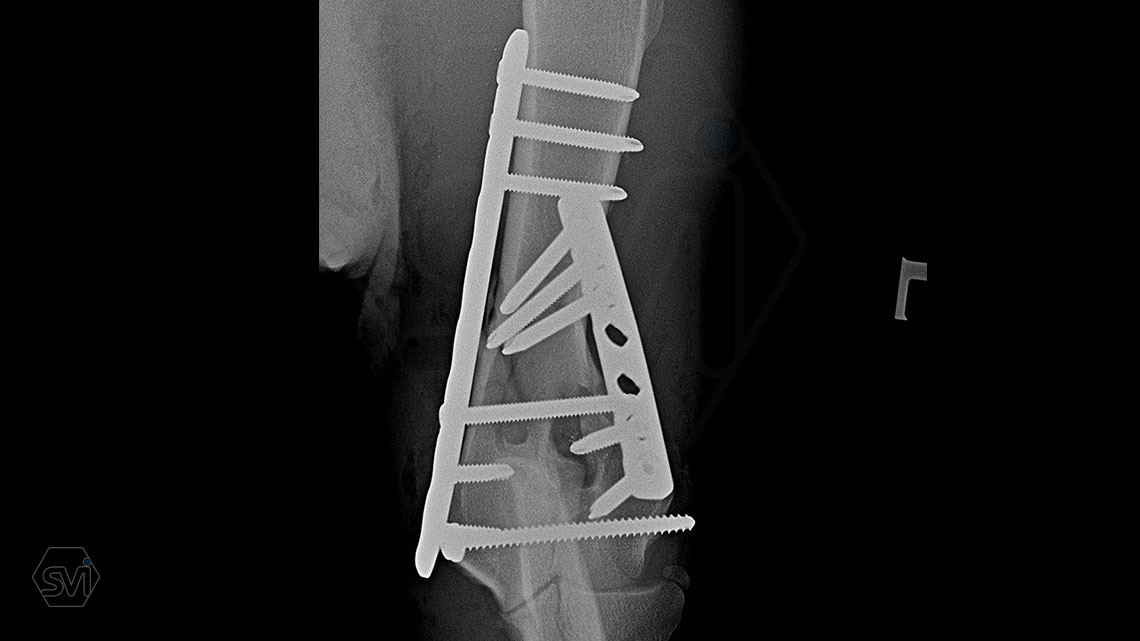

Nightmare for all of us: diastal humeral Y-fracture in a large active dog (German Shepherd)

07 May 2021